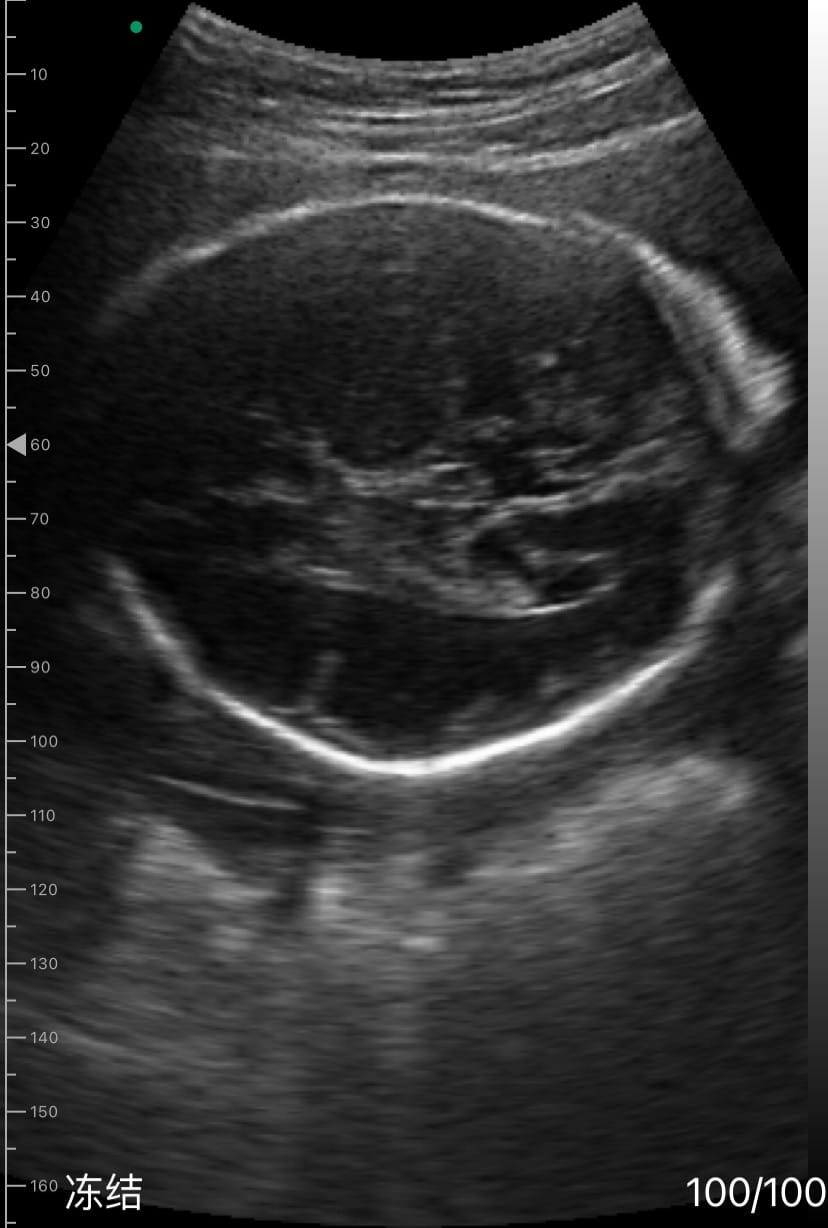

Dr. Sophia Kim, who operates a family practice clinic in Houston, TX, recently used the Dr. Sono Tri-Scan Max to monitor the growth of a fetus at 28 weeks of gestation in a patient with a history of intrauterine growth restriction (IUGR).

By measuring the fetal biparietal diameter (BPD), head circumference (HC), abdominal circumference (AC), and femur length (FL), she confirmed that the fetus was growing appropriately, alleviating the patient's concerns.

In addition to performing detailed biometric measurements to estimate fetal weight, Dr. Kim utilized the color Doppler mode to assess the umbilical cord blood flow, ensuring proper fetal circulation. She also conducted a thorough evaluation of the fetal spine and lateral ventricles to confirm normal development. Amniotic fluid levels and fetal movement were also checked, providing a comprehensive overview of the fetus's well-being.

Dr. Sophia Kim used the DrSono Tri-scan Max to monitor the growth of a fetus at 28 weeks of gestation in a patient with a history of intrauterine growth restriction (IUGR). By measuring the fetal biparietal diameter (BPD), head circumference (HC), abdominal circumference (AC), and femur length (FL), she confirmed that the fetus was growing appropriately, alleviating the patient's concerns.

In addition to performing detailed biometric measurements to estimate fetal weight, Dr. Kim utilized the color Doppler mode to assess the umbilical cord blood flow, ensuring proper fetal circulation. She also conducted a thorough evaluation of the fetal spine and lateral ventricles, confirming normal development. Amniotic fluid levels and fetal movement were also checked, providing a comprehensive overview of the fetus's well-being.

Performed detailed biometric measurements to estimate fetal weight.

Checked for abnormalities in amniotic fluid levels and fetal movement.